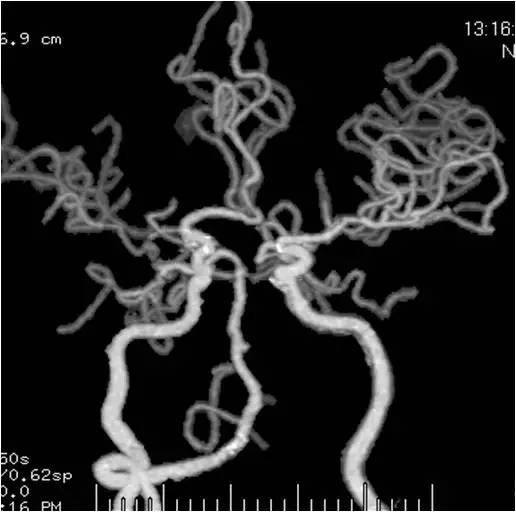

术后CTA:右椎动脉V4段支架通畅(图15)。

图15